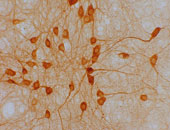

Bis 2050 wird die Anzahl der Morbus Alzheimererkrankungen in Österreich von 70.000 auf 230.000 Fälle pro Jahr ansteigen. Die Gründe: die durchschnittliche Lebenserwartung in unserer Gesellschaft steigt auf über 80 Jahre. Und 30% dieser Altersgruppe erkrankt laut Statistik an Alzheimer, so Humpel. Sein Ziel ist es daher, geeignete "Transportmethoden" zu finden, die diese NGF´s ins Gehirn bringen. "Zur Zeit gibt es nur sehr aufwendige und komplizierte Methoden, wie etwa operative Eingriffe, um diese Wachstumsfaktoren ins Gehirn zu transportieren. Und da die Anzahl der Erkrankungen stetig zunimmt ist es deshalb besonders wichtig, hier einfachere Wege zu finden bzw. diese zu verbessern."